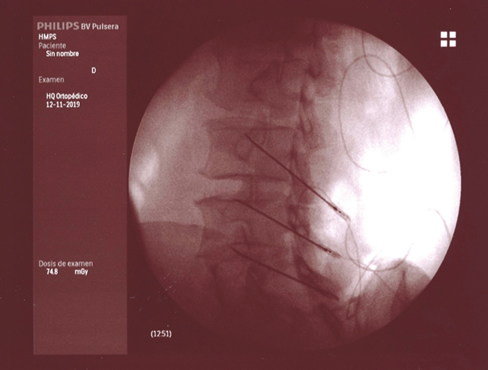

Figura 3